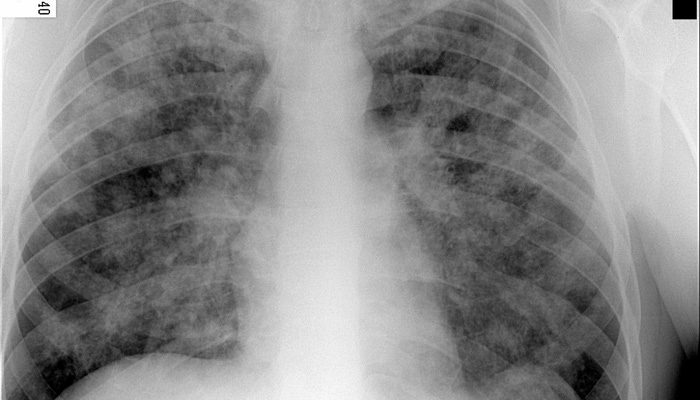

Туберкулез – заболевание инфекционного характера, вызванное микобактериями туберкулеза. Чаще всего они поражают именно легкие, но затрагивают работу всех систем организма человека.

Вот только основная проблема состоит в том, что человек долгое время может не знать, что страдает от туберкулеза, а узнает об этом либо случайно при выполнении рентгенограммы легких, либо при появлении выраженной симптоматики.